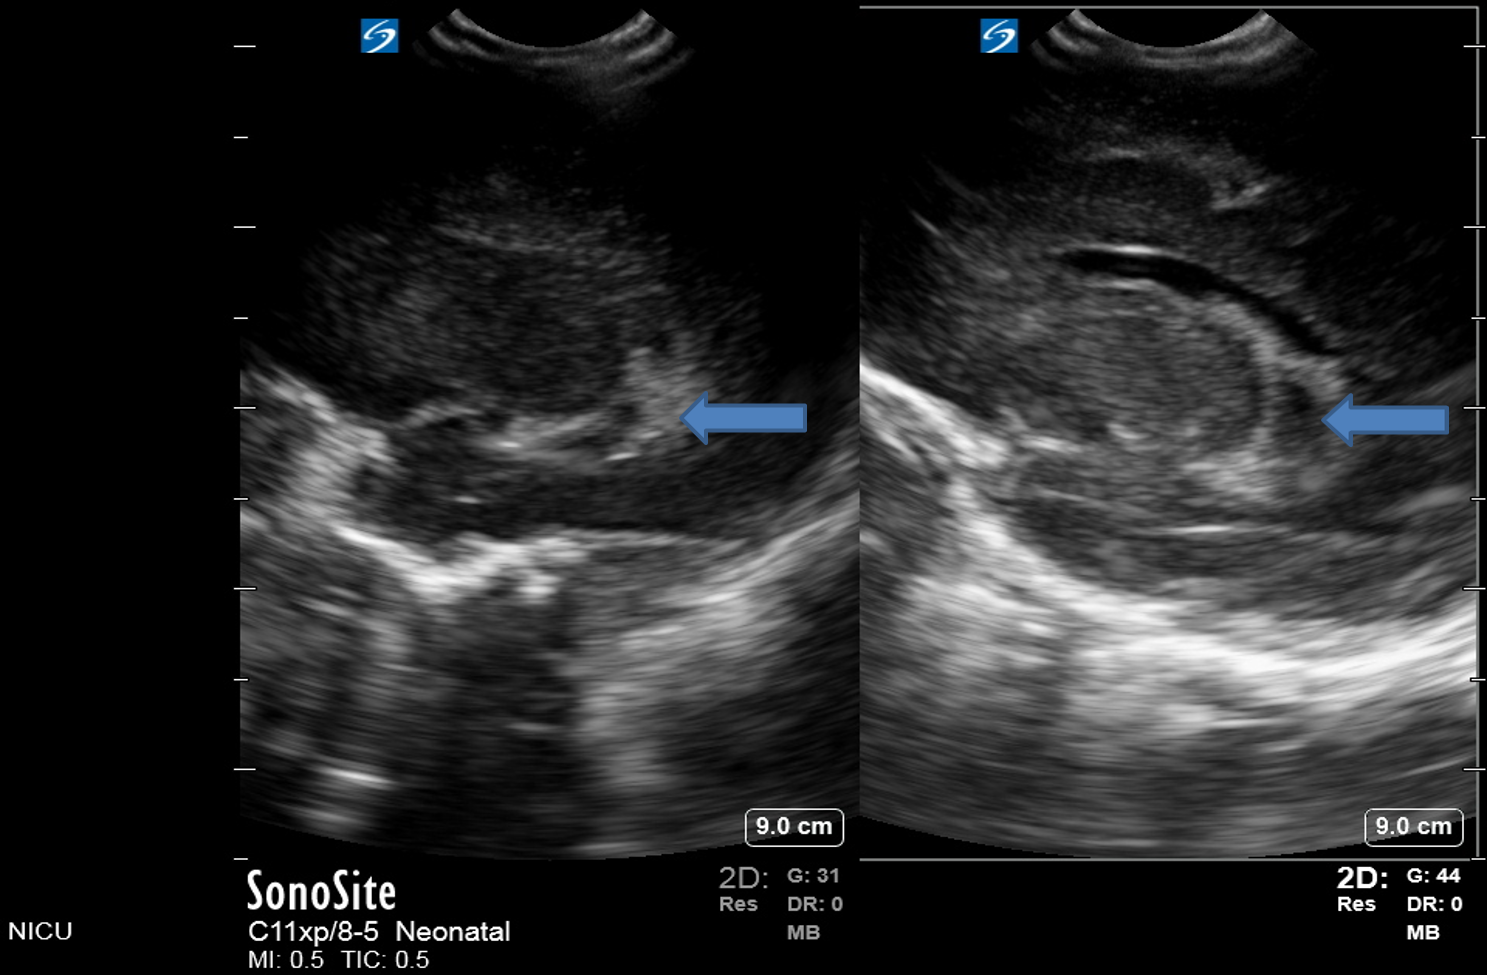

Neonatology Grade 3 IVH Pitfall 1 Image